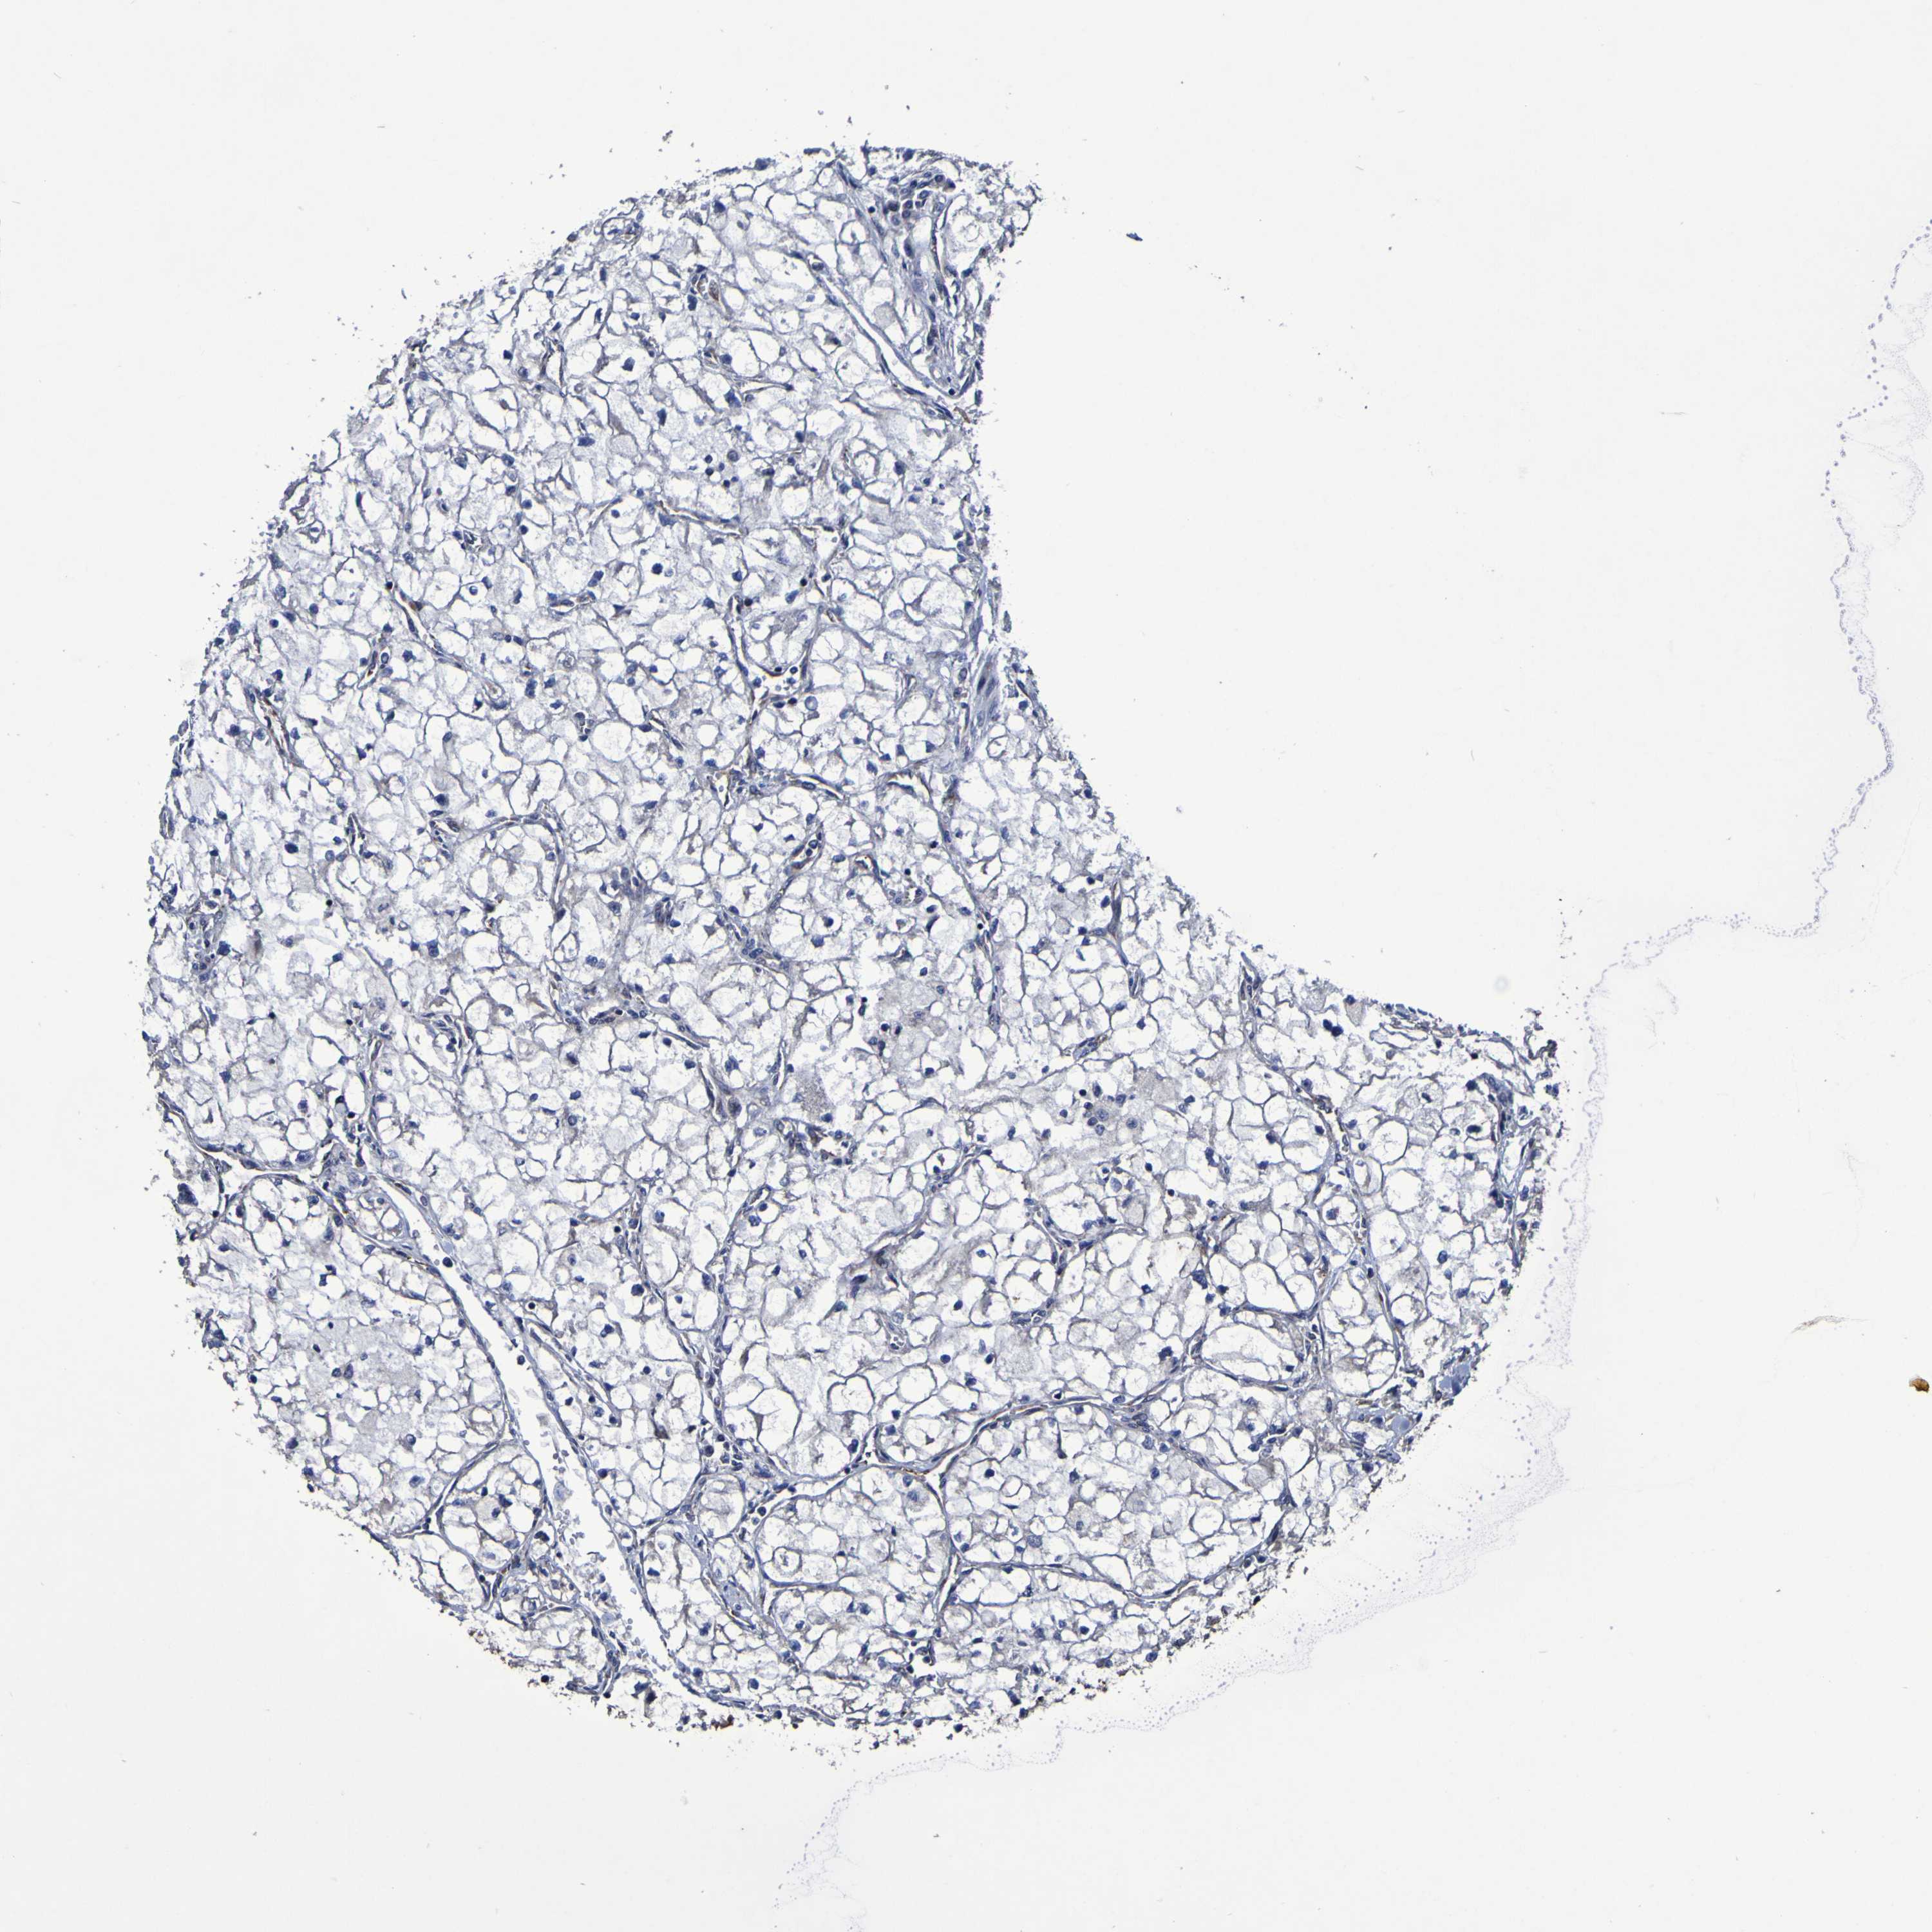

CANCER RENAL CANCER Show tissue menu

KICH TCGA KIRC TCGA KIRC VALIDATION KIRP TCGA PROTEIN RCC CPTAC PROTEIN EXPRESSION